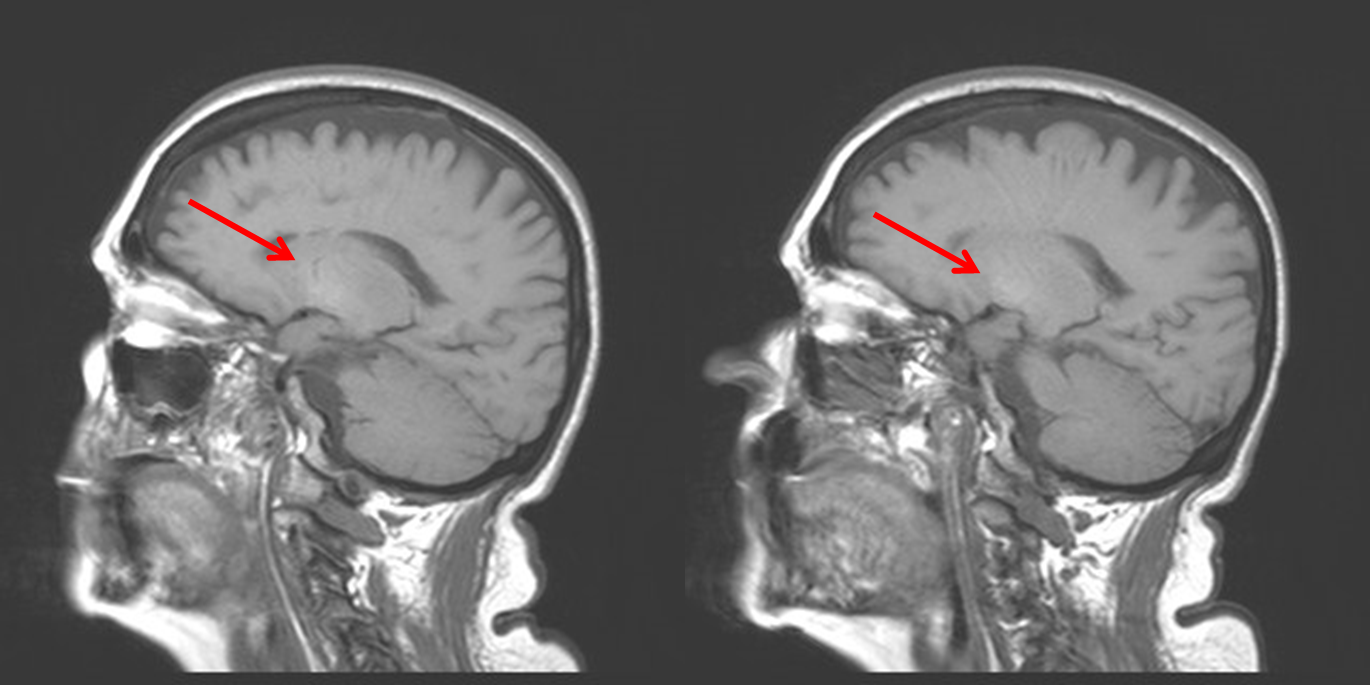

Este caso es una paciente con encefalopatía hepática aguda. En estos casos se puede observar una hiperintensidad en secuencias T1 a nivel del globo pálido (no tengo imágenes axiales) que se ha relacionado desde el punto de vista patogénico con el depósito de manganeso:

Brillante (aumento de la señal, T1 corto): Lípidos, Gadolinio, Metahemoglobina (libre o en los hematíes), sustancias proteináceas, insuficiencia hepática (globo pálido), hipoxia (caudado, putamen) y tumores melanóticos.